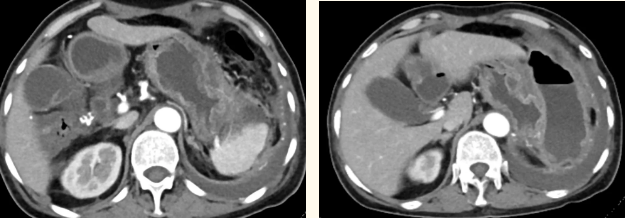

一籌莫展的她終于在病友的介紹下,來到西安國際醫(yī)學(xué)中心醫(yī)院找到蔡磊主任。經(jīng)過詢問病史,查體等,蔡磊主任建議口服索坦治療。3個(gè)月后,李阿姨復(fù)查CT提示胃間質(zhì)瘤較前明顯縮小,大小約10.4cm?6cm。但仍存在消化道出血,營養(yǎng)狀況差,全身無力,骨髓抑制。蔡磊主任隨即將患者收治入院。